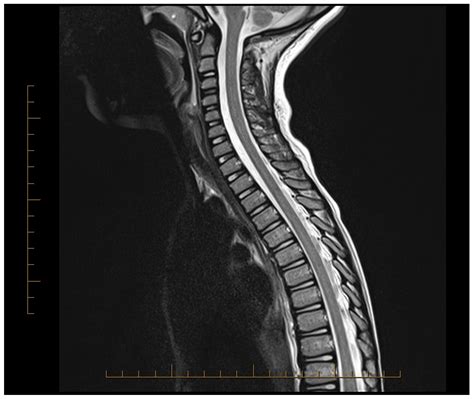

The urgency of Transverse Myelitis treatment cannot be overstated. When a patient presents with symptoms, physicians aim to stop the inflammatory process as quickly as possible. Every hour counts in reducing the potential for permanent nerve damage. Prompt diagnosis through MRI scans and lumbar punctures allows neurologists to initiate therapy, which often changes the trajectory of recovery significantly.